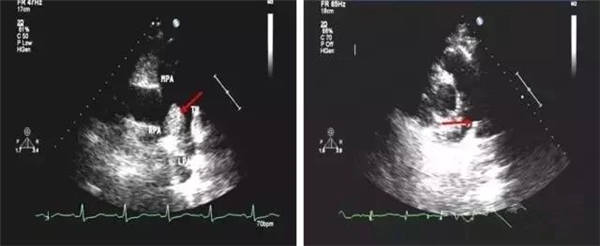

血栓

血栓是血栓性肺栓塞最典型的特征,位于右房或右室中的血栓可形態各異,而位于肺動脈內時則常表現為大塊血栓,從主干延續至一側或雙側肺動脈分支。右肺動脈主干血栓易于顯示,左肺動脈因顯示較短,血栓不易顯示。此外,需注意將血栓與右心系統腫瘤相鑒別。

右心血栓 肺動脈血栓